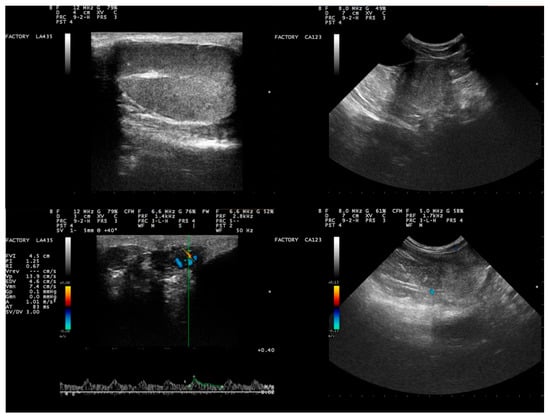

2.1. Animals, Sample Collection, Seminological Examination

3.1. Clinical and Seminological Findings